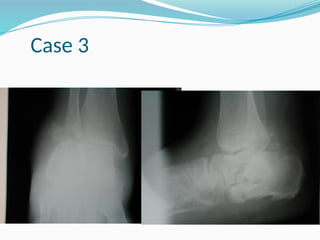

Case 3